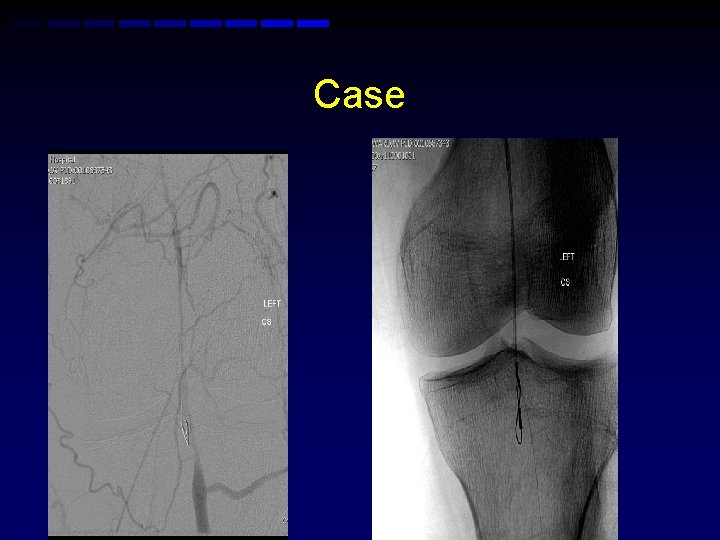

Case • 50 yr old with HTN, hypercholesterolemia and smoker presents with left calf claudication • ABI 0. 72 advised medical therapy • No relief of caludication • Angiogram performed via right CFA

Case • Right retrograde femoral access • Attempt to cross the left popliteal • Subintimal pass • ? Pioneer

Left antegrade puncture

Case